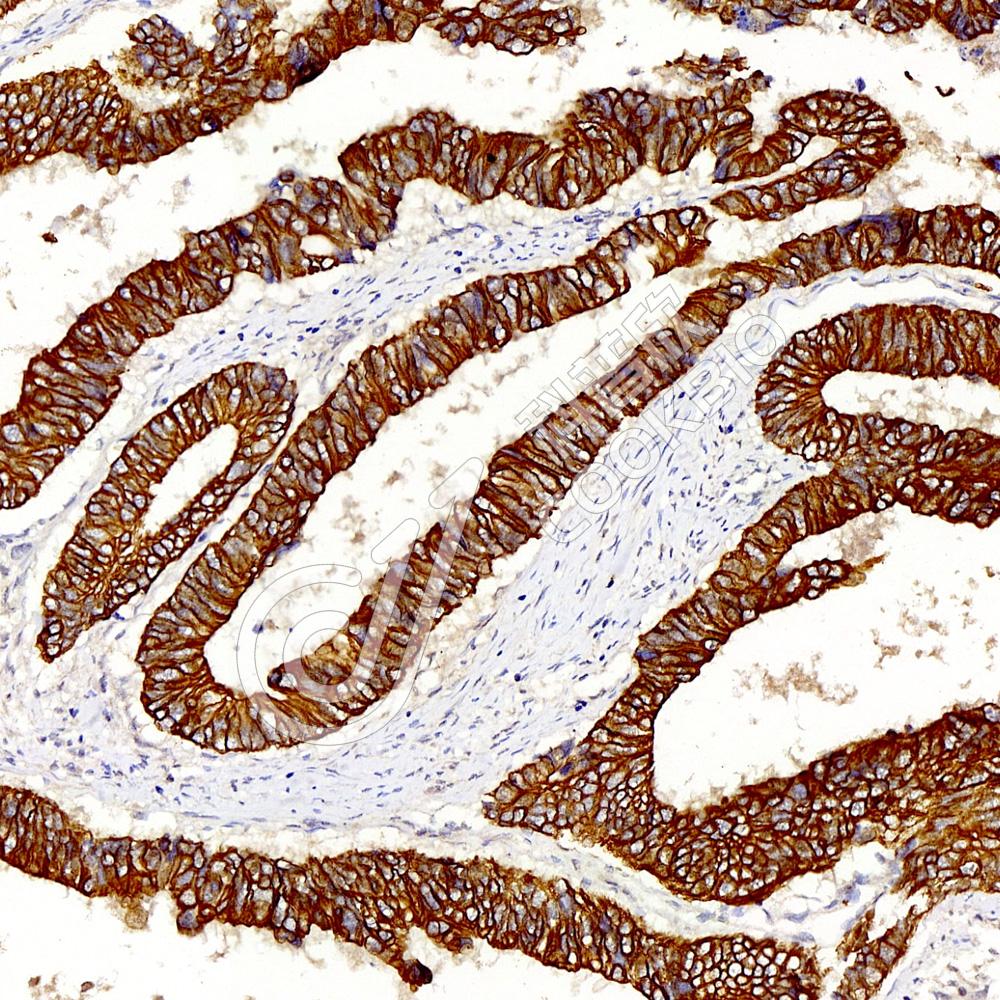

IHC检测Cytokeratin 8蛋白(货号 K133693).

样品: 人结肠癌, 4%多聚甲醛 (货号KSG1101) 固定12-24小时.

抗原修复: 柠檬酸抗原修复液(干粉, pH 6.0) (KSG1201), 98℃, 20分钟.

—抗: 1: 600稀释, 4℃ 孵育过夜.

二抗: S-vision免疫组化多聚二抗(山羊抗兔),即用型 (货号KB3906), 室温孵育20分钟.